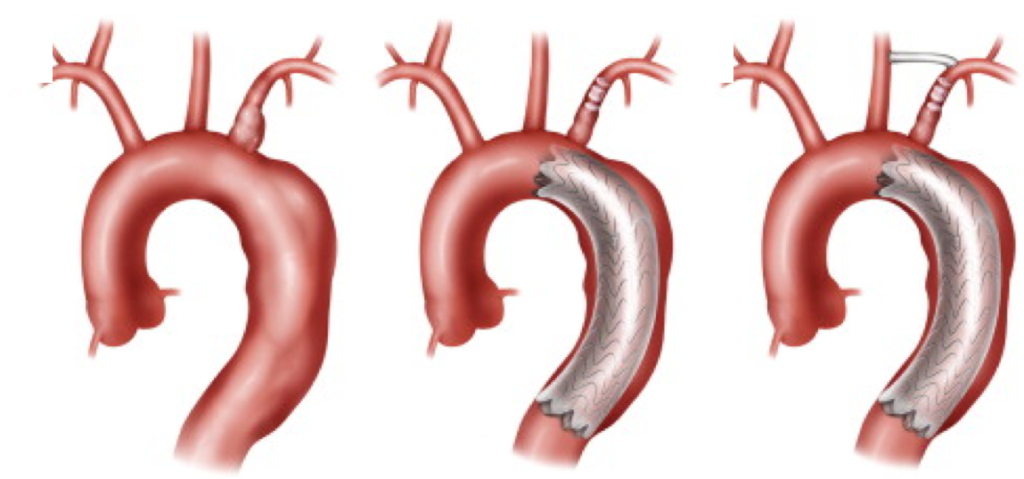

En fonction de la taille de ces anévrismes, de leurs localisations, il peut être proposé un traitement chirurgical. Il y a encore quelques années, ces anévrismes devaient être opérés en faisant de grandes ouvertures, par thoracotomie. Il s’agissait de chirurgies lourdes, parfois avec de nombreuses complications, nécessitant du temps pour récupérer. L’amélioration des prothèses disponibles fabriquées par l’industrie, a permis le développement de prothèses déployées par voie endovasculaire. On parle d’endoprothèses thoraciques ou TEVAR (Thoracic Endo Vascular Aortic Repair). Le concept est de monter sur un stent une prothèse d’où le nom d’endoprothèse couverte. Cette endoprothèse va venir exclure l’anévrisme, limitant ainsi le risque de croissance de ce dernier et donc de rupture.

Dans la grande majorité des cas, la voie d’abord se fait par voie fémorale, sans aucune incision, de manière percutanée. Il sera nécessaire d’injecter de l’iode durant la procédure pour réaliser une angiographie et permettre ainsi le déploiement au bon endroit de la prothèse. La procédure est courte d’environ 1H. Cependant, parfois, en fonction de l’extension proximale de l’anévrisme, il n’est pas rare de devoir faire un pontage entre l’artère carotide et l’artère sous-clavière gauche (pontage carotido-sous-clavier gauche), car le déploiement de l’endoprothèse peut nécessiter d’obturer cette dernière pour garantir un bon résultat. Dans les cas les plus simples, vous resterez hospitalisé(e) une nuit après l’intervention avant votre retour à domicile.